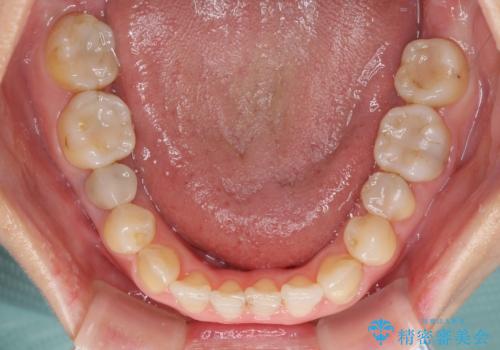

前歯のクロスバイトと治療が必要なむし歯 矯正とセラミックの総合歯科治療

前歯のクロスバイトはインビザラインで改善し、抜歯が必要な部分はインプラントを、その他むし歯が進行している歯はセラミッククラウンによる補綴治療することとしました。

仕事がお忙しく、インビザラインをあまりしっかりと使用できなかったようで、何とか長い期間をかけて歯列を整えることができました。

磨きにくく、何度もむし歯治療を繰り返していた前歯をスッキリと整えることができました。